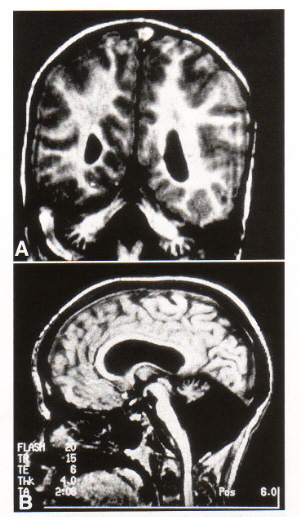

- neuroimaging shows pontocerebellar atrophy

- type Ia shows shrunken cerebellum with firm, prominent foliae

- flattened pons

- cerebral hemispheres unremarkable